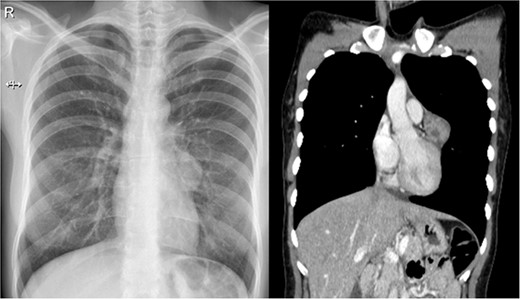

With these results, many diagnoses were among the differential, including pericardial cysts, oncogenic cysts, lymphoma, mesotelioma, metastasic tumors, sarcoma and other mediastinal tumors such as thymoma or teratoma. Therefore, surgical resection was decided through a thoracoscopic approach. A 40 × 30 × 30 mm pearly white, pedunculated and firmly encapsulated tumor was encountered at thoracoscopy. It was near the pericardium and in close contact with the left phrenic nerve. During dissection, it was impossible to retract the phrenic nerve completely; therefore, to avoid the risk of injury, a left posterolateral thoracotomy was performed. Afterward, the entirety of the mass was removed. We dissected it from surrounding structures and completely removed it along with a small portion of the pericardium to which it was attached. The rest of the procedure was completed without complications; a bovine pericardium patch was used to repair the pericardium defect, and finally, a 28 Fr. chest drain was placed (Fig. 2).

Laparoscopy, (a) hard white irregular tumor depends on the pericardium without invasion of the left phrenic nerve. (b) The tumor is adjacent to the lung but not invading it.